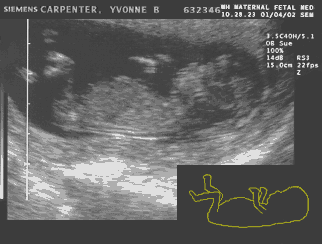

MY's heart at 9 weeks Matt: Because it is still somewhat early the doctor could only intermittently hear the sound of the heartbeat with a Doppler device. This meant another ultrasound and, YES, another picture for the scrapbook!!! All is looking great and now we can see little arms and little legs and that heart — oh what a heart! Man this is exciting — I love it! Thank you Yvonne:-) Unlike the running baby at the top of the page the scan to the right is an unedited ultrasound picture except the heartbeat has been animated to simulate what we saw at the doctor’s office.

Yvonne: We know for a fact now that it has at least one leg and one arm since it was sideways, but the heartbeat was once again the big thrill. The whole embryo looks a little more human and even the proportions are starting to resemble a descendant of our species instead of looking like an alien! The nausea is better but the tiredness is still there. I resumed walking on the treadmill after a week off resting from a minor cold. I try to make myself do it because I feel so tired all the time that it is easier to just drive home and go to bed. But I feel better after some exercise. Besides, I am trying not to gain too much weight too fast. I have already gained 3 pounds since the first doctor’s visit. “They” say you should gain 3 to 4 pounds in the first trimester. However, the end of the first trimester is still 3 weeks away and I don’t want to become the Pillsbury Dough Girl!